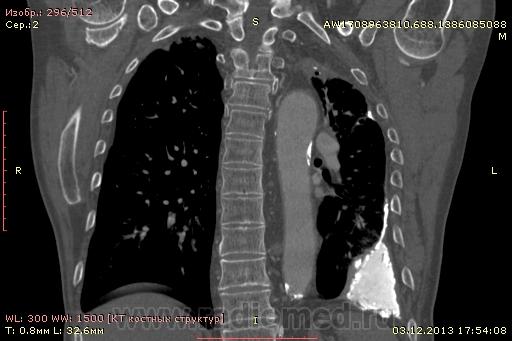

Доброго времени суток уважаемые форумчани! :)Провели исследование КТ грудной клетки с контрастированием, для выявления аневризмы грудного отдела аорты. В результате увидели это:

??? Аневризму честно не вижу (мало опыта в определении аневризм). Тромбоз в бассейне верхней полой вены. В левом легком обызвествленные плевральные шварты? как исход осумкованного плеврита неизвестной давности?

Ребята, вы что, какая жидкость? Чистая известь, посмотрите в костном окне. Отставить натив (в данном случае, хотя для аневризм он обычно нужен). Отставить тромбоз верхней полой вены (потоковые артефакты, не дело вены в артериальную фазу оценивать). Отставить аневризму  аорты, поперчник восходящего отдела на уровне легочного ствола 42мм. А вот легочная гипертензия, здравствуй: поперечник легочного ствола - 37мм, ПЛА - 25мм, ЛЛА - 25мм, НАо - 25-34мм.

Для справки: холестериновые камни имеют плотность менее 100 ед.Н. Имеющаяся хренотень в левом гемитораксе имеет плотность больше костной, до 1500 ед.Н. Вопрос: какая химико-физико-биологическая реакция может способствовать превращению мягинькаво холестерина в термоядерную плевральную лепёшку?)